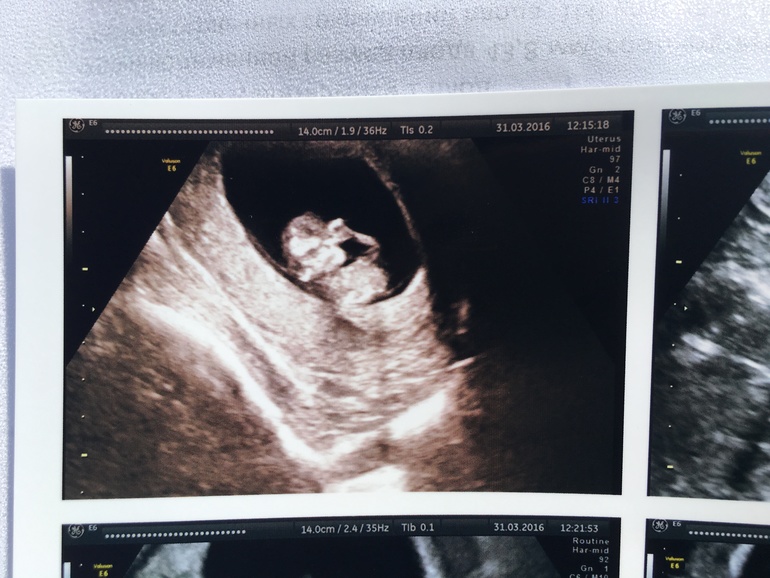

1 скриннинг + фото

Вопросы про УЗИ, обследования и анализы: что, где, как, когда?Была на первом скринниниге, по крови все отлично , Узи тоже отлично . Я не ожидала увидеть маленького человека! Была с мужем, реакция что его, что моя были одинаковые - ступор 😃! Малый ( надеюсь , мальчик будет) спал все Узи ! узистка была довольна сном ребёнка, потому что спокойно все измеряла . Я ожидала увидеть хоть какие-то движения.. Но он спал с рукой во рту .. Все размеры , как по книжке , кровь тоже вся в норме, никаких там отклонений. Показывали и нос, и рот! Офигеть... 5 см , а уже все ,как у человека. Я смотрю , а он пузатый! Говорю врачу, а че он такой пузатый????? Она долго смеялась ... 😃😃 необычные ощущения , но все же никаких там милостей во мне не проснулись , все так же черства к беременности , все так же ноль эмоций. Видимо, буду плохая черствая мамаша.

Я настоятельно просила как-то его расшевелить, включили 3D Узи, долго водила , только тогда он покопошился и снова уснул..